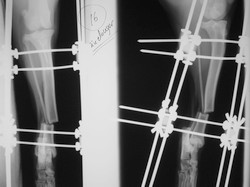

Fijación Externa

Fijación externa en IVOT

PRÁCTICAS CURSO DE FIJACIÓN EXTERNA PERFECCIONAMIENTO.

Elongacion.